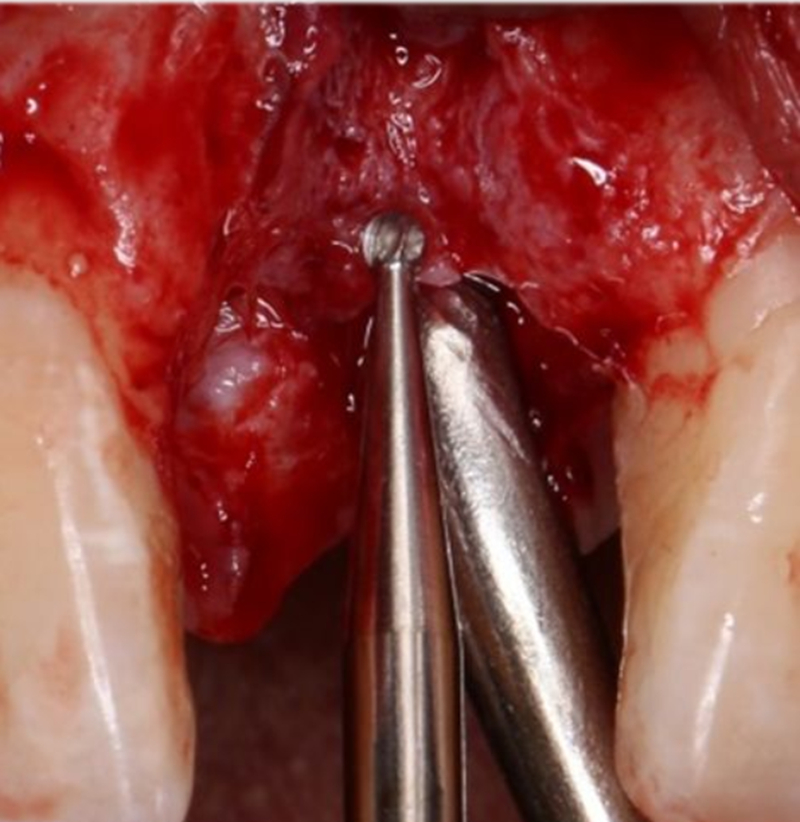

定點

1.4mm小球鉆定點 △

2.3mm中號球鉆打開皮質(zhì)骨△

在易植美實時導(dǎo)航系統(tǒng)中,計算機引導(dǎo)球鉆精準按照術(shù)前設(shè)計定位△